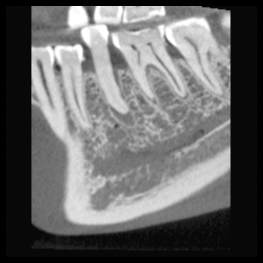

Höga upplösningar och standarddoser är inte alltid nödvändigt – ofta räcker det med lägre dos och upplösning. Planmeca Ultra Low Dose är tillräcklig för att se den mandibulära nervkanalen för implantatplanering och extraktion av visdomstand, till exempel. Allt kan göras med en otroligt låg dos.